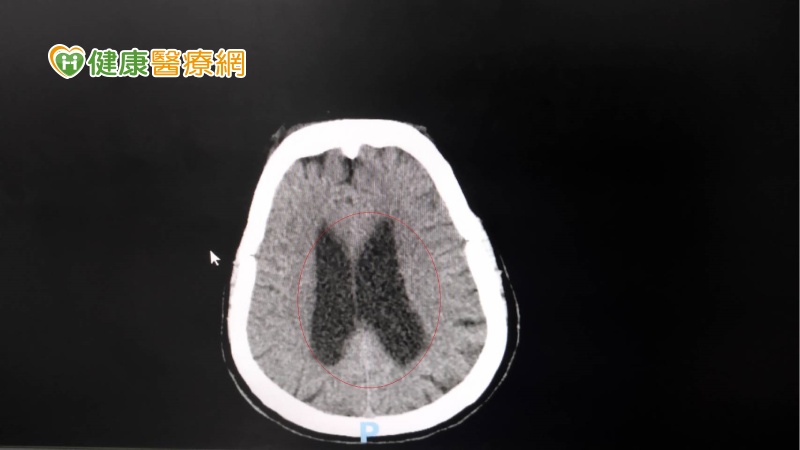

▲周女士的電腦斷層,顯示腦脊髓液過多。(圖/衛福部彰化醫院提供)

賴肇康指出,電腦斷層顯示周女士腦部的腦脊髓液過多,可能是腦脊髓液產生太多或吸收太少,或流動受阻,因其腦壓增加不明顯,被稱為常壓性水腦症。進行腦室腹腔分流手術,在腦室植入細小柔軟導管後經由皮下,將過多的腦脊髓液引流入腹腔,再由人體自然吸收,這是一種永久性的設置,可隨時解決腦脊髓液過多的情況。賴肇康表示,大多數常壓性水腦症的病人是找不出原因的,為原發性常壓性水腦症,少數可追溯病因的有腦部受傷、腦出血、腦中風、腦血管疾病、腫瘤或感染等。建議建立良好的生活作息,如控制三高、少菸酒、適度運動,可避免腦部過早退化。基本上早期診斷、早期治療仍是最好的方式,如果延誤診治,恐對腦部造成不可逆的病變。幸好周女士沒有延誤過久,失智情況得以慢慢回復。